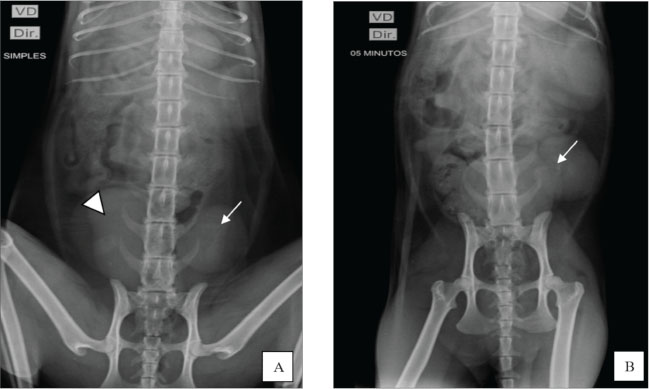

Fig. 1. Ultrasound image showing the left kidney in an ectopic position in the left caudal region of the abdomen, close to the bladder. The organ presented with irregular contours, moderate loss of internal structure, and reduced CM differentiation. Once the patient was stabilized and after considering the absence of the right kidney and atypical location of the left, excretory urography was performed with intravenous administration of iodinated contrast (Omnipaque ®) at a dose of 600 mg/kg via access to the cephalic vein in a rapid bolus to better elucidate the condition. Before contrast media administration, plain abdominal radiographs were performed in ventrodorsal (VD), oblique (the X-ray entered the body through the right ventrolateral side and exited through ventrolateral on the left side), and right lateral projections. All projections showed the absence of the right renal silhouette, while the left kidney was located in the caudal portion of the abdominal cavity, presenting slightly lobulated contours and measuring 3.96 cm in length (Fig. 2A).

Fig. 2. Excretory urography. A) Ventrodorsal plain radiography revealed no visualization of the right renal silhouette, whereas the left kidney (arrow) was identified in the caudal portion of the abdominal cavity, next to the bladder (arrowhead). B) Contrast-enhanced radiograph in the VD projection shows the left ureter filled with contrast (arrow) in the renal pelvis, indicating the beginning of the pyelogram. Greater opacification is noted in the left kidney, which shows signs of slight pelvic dilation. After contrast administration, radiographs were taken in the ventrodorsal, right lateral, and oblique projections at 5, 15, and 30 minutes. At 5 minutes, the image showed the initial phase of the left nephrogram, confirming the absence of the right kidney. At the end of the evaluation, the remaining kidney showed signs of pyelectasis and renal cortical thinning (Fig. 2B). After 24 hours of hospitalization and clinical stabilization, the animal was discharged from the hospital and monitored for 1 month. Four weeks after the absence of clinical signs, the complementary examinations showed stability compared with the examinations at admission. At that time, laboratory findings indicated azotemia: creatinine: 2.6 mg/Dl [reference interval: 0,6–1,6 mg/dl]); urea: 120 mg/dl [reference interval: 10–56 mg/dl]; phosphorus: 5,0 mg/dl [reference interval: 3,5–4,5 mg/dl]) and significant proteinuria (UPC: 0.91). Treatment was instituted with a specific renal diet (Royal Canin Veterinary Diet Renal para Gatos®), enalapril (0.25 mg/kg, BID), and omega-3 supplementation (40 mg EPA + 25 mg DHA/kg). The patient remained clinically stable and was monitored with routine quarterly exams, aiming to monitor the stage II of chronic kidney disease (CKD) according to the International Renal Interest Society (IRIS) classification. Evolution of ureter and renal pelvis dilation in the last evaluation, approximately 3 months after the initial consultation, no changes in renal pelvis dilation were observed compared with the examination previously described in this study. The patient is stable and is being monitored periodically every 2 months. DiscussionTo date, no records have been found describing the simultaneous occurrence of renal agenesis and ectopia in cats, making this report the first to document the condition in cats. It is important to highlight related differential diagnoses, such as solitary crossed renal ectopia, a condition in which one of the kidneys is absent and the ureter crosses the midline. This anomaly has been described in 35 cases in the medical literature and, more rarely, in veterinary literature, including the variant with renal fusion (Allworth and Hoffmann, 1999; Hebel et al., 2020; Maachi et al., 2024). This possibility was ruled out in our case because it was possible to identify the path of the ureter and the position of the remaining kidney through excretory urography. Generally, congenital anomalies of the urinary tract are rarely reported in veterinary medicine and usually manifest through nonspecific clinical signs when they occur (Choi et al., 2012). In the presented case, the nonspecific clinical signs led to laboratory and imaging tests, which were essential to confirm the diagnosis. Renal ectopia is often an incidental finding, with no evident functional impairment (Rajabioun et al., 2017); however, associated alterations, such as hydronephrosis and ectopic ureters, should be investigated. Our report showed alterations compatible with chronicity in the remaining kidney, which may be related to functional renal mass and nephron number reduction. This condition triggers compensatory mechanisms, such as hypertrophy and hyperfiltration, which, over time, can lead to progressive renal damage, culminating in CKD (Brenner et al., 1988). In medicine, the term “solitary kidney” has been used to describe patients who have only one kidney, either due to unilateral renal agenesis, congenital hypoplasia, or surgical removal. A study conducted by Kim et al. (2019) involving patients with a single kidney due to nephrectomy or congenital causes, demonstrated that those who underwent nephrectomy had a higher risk of developing CKD. This difference may be attributed to the early onset of adaptive mechanisms in cases of congenital solitary kidney, which promotes a more efficient compensatory functional response. However, unlike what they reported, the animal in the present case had no history of nephrectomy and was a young patient, but already presented signs compatible with renal chronicity, which shows that functional adaptation may not be sufficient to prevent early development of kidney damage even in congenital cases. In this report, the definitive diagnosis of renal ectopia and agenesis was established based on excretory urography (Chang et al., 2008) and abdominal ultrasonography, without the need for surgical intervention (Heuter, 2005; Dykeman, 2020). Hebel et al. (2020) described the use of excretory urography for renal morphological and functional assessment in a case of crossed renal ectopia in a feline, reinforcing the importance of this modality as a diagnostic tool. Concomitant alterations of the urinary and reproductive systems are possible due to the common embryonic origin in the intermediate mesoderm, which justifies the frequent association between renal and uterine anomalies (Dykeman, 2020). Several cases involving this correlation have already been described in the veterinary literature, such as that of a Persian female with unilateral aplasia of the right uterine horn, ipsilateral renal aplasia, and absence of the corresponding ureter, and that of a 1-year-old cat diagnosed with renal agenesis associated with segmental aplasia of the uterus after surgical reintervention (Goo et al., 2009; Carvalho et al., 2013). However, unlike these cases, the patient in this report had already undergone ovariohysterectomy and did not present any clinical signs of remaining ovaries. The observed alterations were restricted to the urinary system, with emphasis on agenesis of the right kidney and ectopia of the left kidney. The smaller celiotomy incision for ovariohysterectomy is a minimally invasive approach that may result in less tissue trauma and faster recovery (Naiman et al., 2014). However, a potential disadvantage of this technique is its restricted field of view. Unlike wide-incision laparotomy, reduced celiotomy limits complete visual inspection or adequate digital palpation of all abdominopelvic structures (Mayhew et al., 2014). In the described case, an incision of 3 cm (1.18 inches) was performed, which significantly restricted the visualization and manipulation of intra-abdominal structures. This possibly prevented the identification of the ectopic kidney, which was located adjacent to the bladder, and the absence of the contralateral kidney during the surgical procedure. Although renal ectopia is asymptomatic in many cases, this congenital anomaly should be considered among the differential diagnoses when abdominal masses located in the caudal region are present, especially when observed on plain radiographs. Despite its limitations in detailed anatomical assessment, abdominal radiography can efficiently exhibit deviations from the expected renal topography. The identification of an ectopic kidney can be challenging in the absence of clinical signs or obvious functional changes, as demonstrated in the present report (Webb, 1974). In these cases, additional imaging tests, such as excretory urography, are essential for diagnostic confirmation, offering a less invasive alternative to exploratory laparotomy. To date, the reported case represents the first documented case of this anomaly in felines, contributing to the understanding of congenital urinary tract malformations in small animals. The scarcity of similar reports makes estimating prognosis and survival rates difficult. The patient’s clinical follow-up demonstrated good general condition, with tests compatible with stage II CKD, according to the IRIS classification (2023). The patient had persistent azotemia, mild arterial hypertension (150 mmHg), and significant proteinuria (urine protein-to-creatinine ratio, UPC: 0.91), with a urine specific gravity (USG) of 1.010. Given these findings, treatment was instituted with a specific renal diet (Royal Canin Veterinary Diet Renal para Gatos®), enalapril, and omega-3 fatty acid supplementation, as recommended by IRIS (2023). The use of angiotensin-converting enzyme inhibitors contributed to the control of proteinuria and arterial hypertension, lowering the risk of organ damage. Continuous clinical and laboratory monitoring was performed in patients with renal agenesis and ectopia, focusing on the management of chronic kidney disease. Stage II indicates impaired renal function even in the absence of clinical signs, justifying the need for periodic monitoring. This protocol includes comprehensive laboratory evaluations, SBP measurement, and imaging tests to monitor disease progression and detect early complications associated with ureteral changes. Due to their abnormal location, ectopic kidneys are more susceptible to complications such as uroliths, hydronephrosis, and pyelonephritis due to inefficient urinary drainage (Rajabioun et al., 2017). In this case, the drainage was impaired, resulting in pyelectasis and subsequent CKD diagnosis. Proper clinical staging and regular follow-up are essential for effective management and to prevent worsening of the condition (Webb, 1974; Arena et al., 2007). ConclusionThe coexistence of renal agenesis and ectopia is rare in humans and has not been reported in felines in the veterinary literature. Despite its rarity, this condition is compatible with life when diagnosed early and continuously monitored. Diagnostic confirmation requires imaging tests, such as abdominal ultrasound and contrast-enhanced radiographs, to identify the absence of a kidney, the ectopic location of the remaining kidney, and any associated urinary tract changes. AcknowledgmentsThe authors express their gratitude to Dr. Lucas Facundo from Radiosonar for kindly providing the ultrasound image and to Dr. Antonia Iraina from Veter for providing the contrast radiograph image. Conflict of interestThe authors declare no conflict of interest. FundingThis study received no specific grant. Authors' contributionsYury Carantino Costa Andrade: Original draft, Investigation, Data curation, Conceptualization. Cicera Paloma de Sousa: Writing, review, and editing. Anne Karoline Mendes da Silva: Writing, reviewing, and editing. Lara Vilela Soares: Writing, reviewing, and editing. Maria Eduarda Raffaini de Oliveira Cunha: Writing, review, and editing. Suellen Rodrigues Maia: Writing, review, and editing. Marian Acácia Fornazier Magalhães: Writing, review, and editing. Patrícia Alves dos Reis: Writing, review, and editing. Leandro Zuccolotto Crivellenti: Writing, review, and editing, validation, and supervision. Data availabilityAll data generated or analyzed during this study are included in this published article. ReferencesAllworth, M.S. and Hoffmann, K.L. 1999. Crossed renal ectopia with fusion in a cat. Radiol. Ultrasound 40(4), 357–360; doi:10.1111/j.1740-8261.1999.tb02125.x Arena, F., Arena, S., Paolata, A., Campenni, A., Zuccarello, B. and Romeo, G. 2007. Is a complete urological evaluation necessary in all newborns with asymptomatic renal ectopia?. Int. J. Urol. 14(6), 491–495; doi:10.1111/j.1442-2042.2007.01764.x Babu, C.S.R., Agrawal, B., Sharma, V., Kumar, A., Jain, R. and Gupta, O.P. 2015. Crossed renal ectopia without fusion: a multidetector computed tomography study. Int. J. Anat. Res. 3(4), 1585–1592; doi:10.16965/ijar.2015.293 Brenner, B.M., Garcia, D.L. and Anderson, S. 1988. Glomeruli and blood pressure. Less of one, more of the other?. Am. J. Hypertens. 1(4 Pt 1), 335–347. Carvalho, F.R., Wartluft, A.N. and Melivilu, R.M. 2013. Unilateral uterine segmentary aplasia, papillary endometrial hyperplasia, and ipsilateral renal agenesis in a cat: a case report. Feline. Med. Surg. 15(4), 349–352; doi:10.1177/1098612X12467786 Chang, J., Jung, J.H., Yoon, J., Choi, M.C., Park, J.H., Seo, K.M. and Jeong, S.M. 2008. Segmental aplasia of the uterine horn with ipsilateral renal agenesis in a cat. J. Vet. Med. Sci. 70, 641–643; doi:10.1292/jvms.70.641 Choi, J., Lee, H., Lee, Y. and Choi, H. 2012. Simple ectopic kidney in three dogs. J. Vet. Med. Sci. 74, 1373–1375. Cohen, H.L., Kravets, F., Zucconi, W., Ratani, R., Shah, S. and Dougherty, D. 2004. Congenital genitourinary system abnormalities. Semin. Roentgenol. 39(2), 282–303; doi:10.1053/j.ro.2003.12.005 Cuckow, P.M., Nyirady, P. and Winyard, P.J.D. 2001. Normal and abnormal development of the urogenital tract. Prenat. Diagn. 21(11), 908–916; doi:10.1002/pd.214 De Tomasi, L., David, P., Humbert, C., Silbermann, F., Arrondel, C., Tores, F., Fouquet, S., Desgrange, A., Niel, O., Bole-Feysot, C., Nitschké, P., Roume, J., Cordier, M.P., Pietrement, C., Isidor, B., Khau Van Kien, P., Gonzales, M., Saint-Frison, M.H., Martinovic, J., Novo, R., Piard, J., Cabrol, C., Verma, I.C., Puri, R., Journel, H., Aziza, J., Gavard, L., Said-Menthon, M.H., Heidet, L., Saunier, S. and Jeanpierre, C. 2017. Mutations in GREB1L Cause Bilateral Kidney Agenesis in Humans and Mice. Am. J. Hum. Genet. 101(5), 803–814; doi:10.1016/j.ajhg.2017.09.026 Dykeman, D. 2020. Segmental uterine aplasia and ipsilateral renal agenesis in a ragdoll cat. Can. Vet. J. 61, 424–426. González Mediero, J.A., García, J., Tinajas Saldaña, A., Santiago, D., González Vicente, A.M. and Urrutia Avisrros, M. 1997. Unilateral renal agenesis associated with pelvic renal ectopy. Arch. Esp. Urol. 50(9), 1004–1006. Goo, M.J., Williams, B.H., Hong, I.H., Park, J.K., Yang, H.J., Yuan, D.W., Lee, H.R., Hong, K.S., Ki, M.R. and Jeong, K.S. 2009. Multiple urogenital abnormalities in a Persian cat. Feline Med. Surg. 11(2), 153–155; doi:10.1016/j.jfms.2008.04.007 Hebel, M., Ruszkowski, J.J., Giza, E. and Pomorska-Mól, M. 2020. Crossed renal ectopia with fusion in a pelvic inlet area, atypical portal vein and coccygeal deformation in a young female cat. BMC Vet. Res. 16(1), 314; doi:10.1186/s12917-020-02535-9 Heuter, K.J. 2005. Clin. Tech. Excretory urography Small Anim. Pract. Small. Anim. Pract. 20(1), 39–45. International Renal Interest Society (IRIS). 2023. IRIS Staging of Chronic Kidney Disease (CKD). Available via https://www.iris-kidney.com/guidelines/staging.html Kim, S., Chang, Y., Lee, Y.R., Jung, H.S., Hyun, Y.Y., Lee, K.B., Joo, K.J., Yun, K.E., Shin, H. and Ryu, S. 2019. Solitary kidney and risk of chronic kidney disease. Eur. J. Epidemiol. 34(9), 879–888; doi:10.1007/s10654-019-00520-7 Maachi, Y., Babty, M., Fouimtizi, J., Slaoui, A., Karmouni, T., El Khader, K., Koutani, A. and Ibn Attya Al Andaloussi, A. 2024. Crossed renal ectopia: a case report and literature review. Urol. Case. Rep. 54, 102690; doi:10.1016/j.eucr.2024.102690 Mayhew, P.D., Mayhew, K.N., Shilo-Benjamini, Y., Kass, P.H. and Pascoe, P.J. 2014. Prospective evaluation of access incision position for minimally invasive surgical organ exposure in cats. J. Am. Vet. Med. Assoc. 245(10), 1129–1134; doi:10.2460/javma.245.10.1129 Morita, T., Michimae, Y., Sawada, M., Uemura, T., Araki, Y., Haruna, A. and Shimada, A. 2005. Renal Dysplasia with Unilateral Renal Agenesis in a Dog. J. Comp. Pathol. 133(1), 64–67; doi:10.1016/j.jcpa.2005.01.002 Naiman, J.H., Mayhew, P.D., Steffey, M.A., Culp, W.T.N., Runge, J.J. and Singh, A. 2014. Laparoscopic treatment of ovarian remnant syndrome in dogs and cats: 7 cases (2010-2013). J. Am. Vet. Med. Assoc. 245, 1251–1257; doi:10.2460/javma.245.11.1251 Oliveira, E.L.R., Costa, A.L.M., Borges, M.F., Nemer, V.C., Baldissera, R.A., Vasconcelos, M., Pereira, K.H.N.P. and Schimming, B.C. 2020. Unilateral Renal Agenesis in P. chilensis in Chilean-Flamingo. Acta Sci. Vet. 48, 496; doi: 10.22456/1679-9216.100607 Plutecki, D., Kozioł, T., Bonczar, M., Ostrowski, P., Skorupa, A., Matejuk, S., Walocha, J., Pękala, J., Musiał, A., Pasternak, A. and Koziej, M. 2023. Renal agenesis: a meta‐analysis of its prevalence and clinical characteristics based on 15,641,184 patients. Nephrology 28, 525–533. Rajabioun, M., Salari Sedigh, H. and Mirshahi, A. 2017. Bilateral simple ectopic kidney in a cat: a case report. Forum 8(2), 175. Webb, A.I. 1974. Renal ectopia in a dog. Aust. Vet. J. 50, 519–521; doi:10.1111/j.1751-0813.1974.tb14059.x/